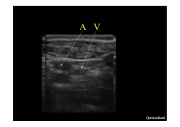

AV

Quintaliani